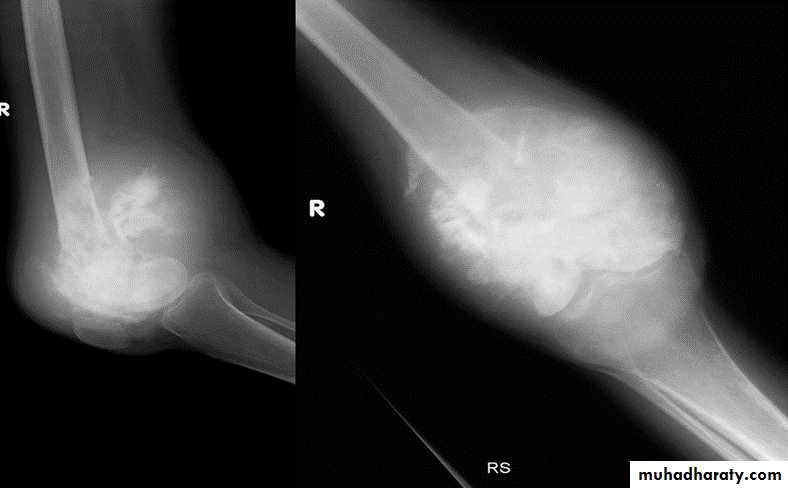

Ewings Sarcoma

Highly malignant with tendency to metastasize.Age: children.

Site: shaft of long bone.

Findings:

ill-defined destruction with onion peal periosteal reaction.

Ewing's sarcoma. Sunray speculation Onion peel appearance

Giant cell tumor:Slowly growing , locally invasive, rarely metastasize.

Age: after closure of epiphysis (20-40 years).

Site: around knee & wrist joints.

lytic, expansile lesion,

Sub articular in location,

Not clearly defined margin,

thinning of the cortex (sometimes with destruction of cortex)